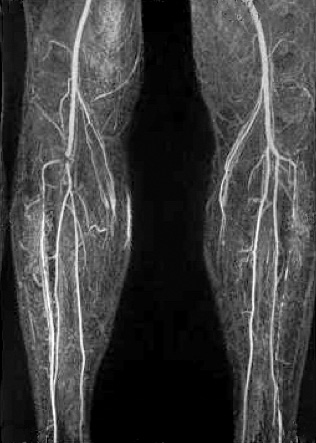

МРТ–ангиография.

Этот метод дает возможность получения трехмерного изображения сосудов без лучевой нагрузки. В применении к варикозному расширению вен этот метод используется для изучения глубокой венозной системы нижних конечностей и малого таза, при подозрении на наличие сосудистых мальформаций, сосудистых опухолей.

Диагностика варикоза